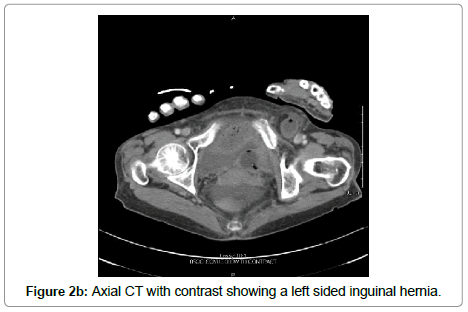

A 76 year-old hispanic lady (BMI: 19.38) with a past medical history significant for poorly controlled diabetes mellitus type II presented to the emergency department with an acute abdomen. Her pain started a week prior and was progressively worsening, which prompted her to come to the emergency department. Her last bowel movement was 4 days prior to admission without hematochezia. On admission, the patient was experiencing nausea, vomiting, chills, altered mental status, and decreased appetite. Her vitals showed a maximum temperature of 37.5°C with a heart rate of 101 beats per minute, respiration rate of 18 breaths per minute, and blood pressure was initially 57/33 mmHg which was stabilized to 118/55 mmHg after resuscitation with intravenous (IV) fluids. She was saturating at 96% on room air. Her labs showed a white blood cell count of 2.5 thousand/uL, bicarbonate of 19 mEq/L, glucose of 200 mg/dL, anion gap of 18, BUN 26 mg/dL, creatinine of 1.2 mg/dL, and lactic acid of 4.7 mMol/L. On physical exam, the patient appeared cachectic and in moderate distress. Her abdomen revealed absent bowel sounds and was distended, rigid, tympanic to percussion, and diffusely tender to palpation. Subsequent chest X-ray revealed pneumoperitoneum (Figure 1). Computed tomography (CT) scan of the abdomen and pelvis with contrast revealed small bowel proximal to the terminal ileum within the left inguinal ring (Figures 2a and 2b). Multiple loops of small bowel demonstrated decreased wall enhancement with ischemic changes. There was also a large amount of free fluid in the abdomen. We had a high suspicion for a perforated small bowel obstruction due to incarcerated and strangulated left inguinal hernia. The peritonitis led to septic shock, therefore she was stabilized with 6 L of IV normal saline, pressors, and piperacillin/tazobactam. The risks, benefits, complications, and alternatives were discussed with the patient and her family, in which they chose to proceed with surgery.